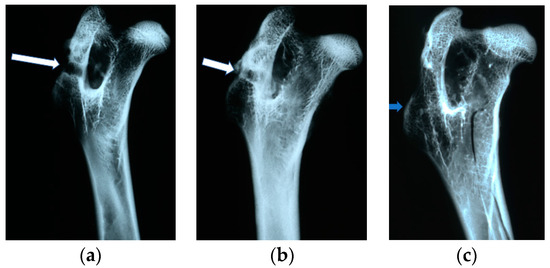

4.4. Radiological Evaluation

In X-ray imaging, all the implants remained translucent and invisible. At the first month after implantation, it was observed that the implant canals with implanted materials, PLGA + IGF1 and PLGA/PHB + IGF1, were partially filled with callus, which was partially sclerotic. In the implantation locations for the control materials, PLGA and PLGA/PHB, only traces of calluses were observed. All openings at the implantation sites were open. After two months, a continuation of filling with calluses was observed in the implant canals of the PLGA + IGF1 and PLGA/PHB + IGF1 samples. The implant holes remained open in the PLGA + IGF1 samples, while, in the PLGA/PHB + IGF1 samples, most holes were closed with osseous lamina. In individual control samples (PLGA/PHB), a marginal amount of osteosclerosis or osteolysis was observed. After three months, the implant canals were closed entirely or, in individual samples, partially closed with spongy calluses. In the PLGA implant materials, the implant canals were closed, except in some individual samples, in which the canals were partially filled with calluses from the bottom, while the entrances remained open. Six months after implantation, the implant canals were filled with spongy calluses. In individual control samples, trace osteolysis was recorded. All implant holes were closed by osseous lamina. In subsequent post mortem examinations (after nine to 12 months), the macroscopic images were similar. There were no periosteal reactions in the autopsy period. Radiographic images of changes within the groups are presented in Figure 4. The persistent differences between the control groups and the IGF1 tested groups are shown in Figure 5.

Figure 4. Radiological images after implantation of the tested materials: (a) 1 PLGA after one month. Visible implantation borehole. No callus. Slight periosteum around the implant. (b) PLGA after two months. Implantation borehole closed with a bone cap. Channel partially filled with callus. (c) PLGA after 12 months. Implantation channel invisible, overgrown with bone trabeculae.

Molecules 22 01852 g004